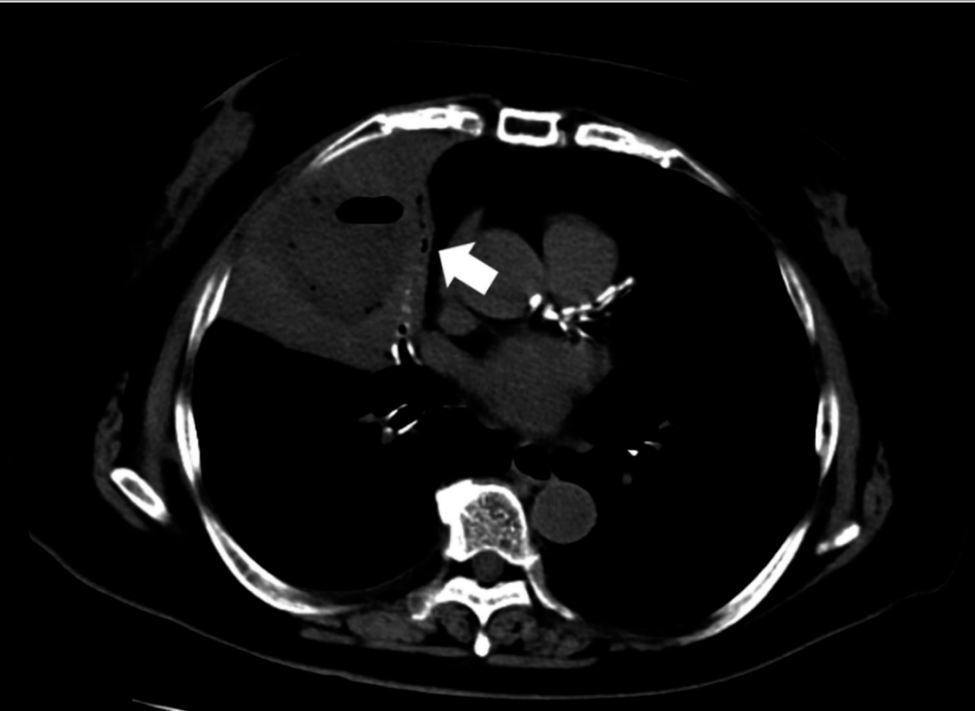

PD术后14个月发现肺转移,予S-1化疗2周期。2个月后发现肝转移,改用GnP二线化疗。8周期化疗后肺肝转移灶均呈缩小趋势,遂行肝切除术。CT显示肝第5段病灶(图5)。

图5. 病例3CT显示肝第5段表浅部位早期强化小病灶(箭头)